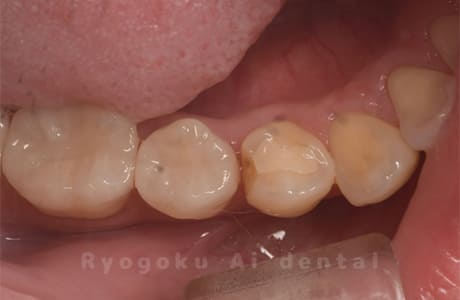

Case08

-

- 原因

- 虫歯

- 治療内容

- セラミックインレー

- 治療費用

- 77,000円

奥歯の黒い点が気になるということで来院された患者さんです。白い詰め物を外したところ、虫歯が中で大きく広がっていたため、患者さんと相談し、セラミックインレーで治療を行いました。

<リスク・副作用>

過度の咬合や衝撃で割れることがあります。